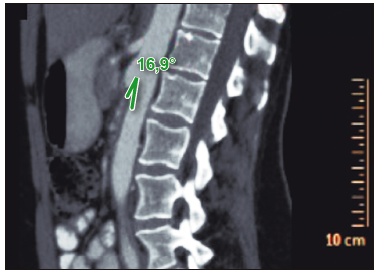

Figura 1. En el corte sagital de la TC de abdomen con contraste se observa la

reducción del ángulo aorto-mesentérico de 16,9°